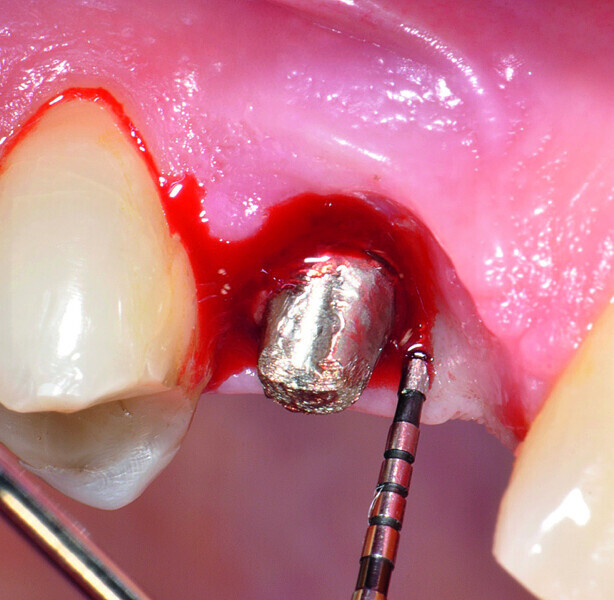

Fig. 1a: Implant in position #14 affected by peri-implantitis: periimplant probing a) with the prosthetic crown in situ and b) after prosthetic crown removal.